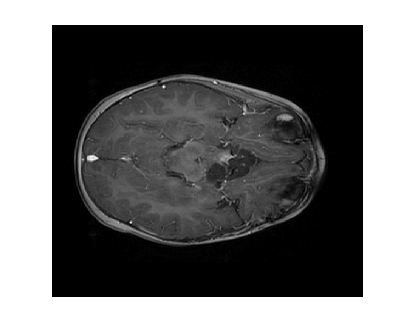

Figure 3 displays the reconstruction MSNR for the various test cases as cataloged in Table 1. Figures 1 and 2 display some examples of reconstructed images for cases of interest.

The image recovery results for the phantom image experiment were quite extreme, as shown in Figure 3. We split all the cases into two groups: a group with high MSNR and a group with low MSNR. While grouping these cases we noticed that all of the cases that used LACS-MRI were classified as high MSNR, outperforming the cases that used L1-W. This is expected since L1-W is unable to utilize a reference image. Case 1 and Case 2 had the best recovery of the phantom image out of all methods. Case 5, which also uses the same adaptive sampling density as cases 1 and 2, also shows accurate recovery. We notice that for cases with (Case 1, Case 2, and Case 5) and (Case 17, Case 18, and Case 19) as their adaptive density sampling methods, the RSNR is high when using the LACS-MRI algorithm. combined with performs better than combined with . Accordingly, we see that the adaptive density function plays a key role in the LACS-MRI algorithm.

Note that when we use only variable density sampling, we get the worst performance. Again, this is not surprising since this means we do not benefit from the use of a reference image. Recovery can be improved by using but it does not compare favorably with or . On the other hand, L1-W recovered the image poorly. Surprisingly, purely adaptive cases with and (Case 13 and Case 14) performed the best among all combinations. In L1-W, we initialize to be the same as which is why both show almost the exact same performance.

The phantom image that we used in the previous experiment is flat and has less texture while the brain images has a lot of wrinkles and complex shapes. While the phantom image is small, the brain image is too large to calculate efficiently. Thus, we conducted an experiment in the same setting as the phantom image excluding cases using : cases 6 through 8 and 14 through 16. In this experiment, contrary to results for the phantom image experiment, L1-W performs better than LACS-MRI. For example, Case 3 performed the best among cases using LACS-MRI but it performs worse than 6 cases that use L1-W. Interestingly, one of the cases that shows an outstanding image recovery purely uses with L1-W. However, purely using with L1-W shows a dramatically worse performance. In conclusion, we are unsure why each combination of mixed PDFs and reconstruction algorithm perform differently based on the images processed, but this differing behavior is crucial to highlight for practical applications. We conjecture that the texture of the image is one factor that decides the performance of each algorithm. In the future, we may explore this conjecture and analyze why this happens.